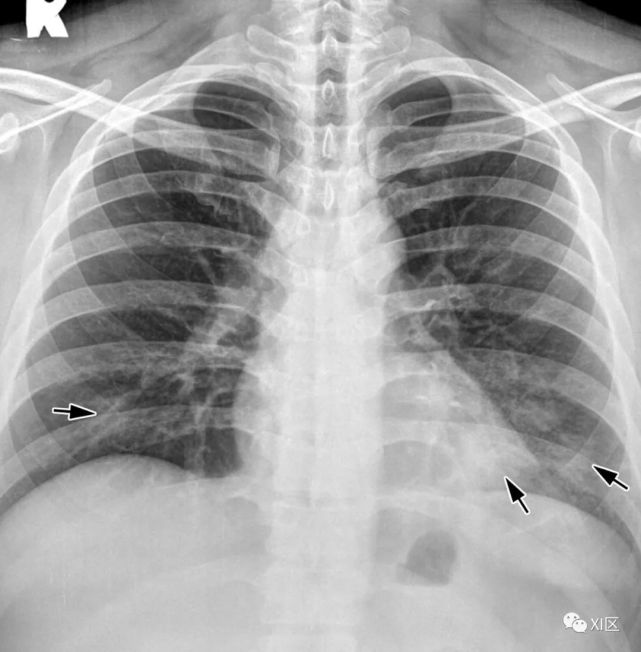

图8 20岁男子因腺病毒感染引起肺炎,伴有发热、咳嗽和呼吸困难。

(上) 最初的胸片显示左中下肺和右下肺区有不明确的斑片状实变和GGO(箭头)。同一天在叶间支气管水平(中)和肺下静脉水平(下)上获得的轴位胸部CT图像(厚度为5mm)显示不明确的斑片状GGO(箭头)和大叶实变(箭)。

Koo H J , Lim S , Choe J , et al. Radiographic and CT Features of Viral Pneumonia[J]. Radiographics, 2018, 38(3):719-739.